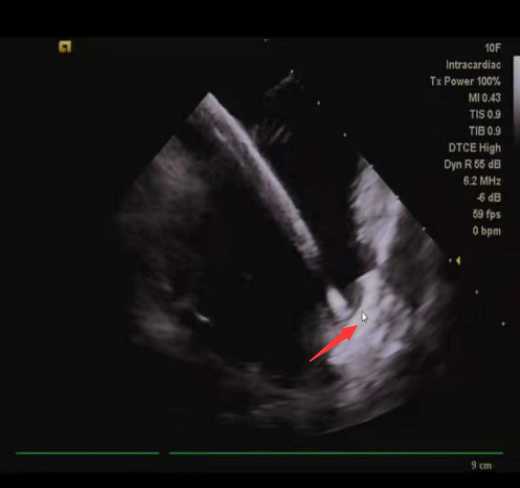

术中,张志辉教授带领罗文治主治医师及邓煦主治医师,首先对病人进行房颤的环肺静脉电隔离及左心房基质改良,随后应用心腔内超声,对患者的左心耳形态及直径大小进行了精确测量,结合X线下造影的影像,使用了ACP20mm的左心耳封堵器对患者左心耳进行封堵,封堵器到位顺利,一次性展开成形,再次应用腔内超声对展开后的封堵器进行测量,封堵器完美封堵左心耳开口,且对左心耳附近的结构没有影响,遂释放封堵器。整个手术过程患者均在清醒状态下,术中患者各项生命体征平稳。

房颤肺静脉隔离

心腔内超声下左心耳封堵器(箭头所指)